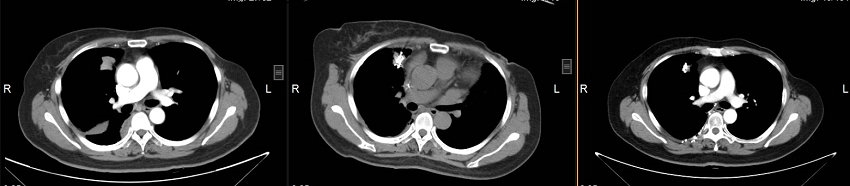

乳腺癌纵隔及胸壁转移氩氦刀冷冻消融联合放射性粒子植入治疗前、中、治疗后对比

经过冷冻消融、碘-125放射性粒子植入术,并4个周期全身化疗后,病灶明显缩小。祁阿姨原本确诊时沉重心终于如释负重,阿姨久违的笑容再次出现了。